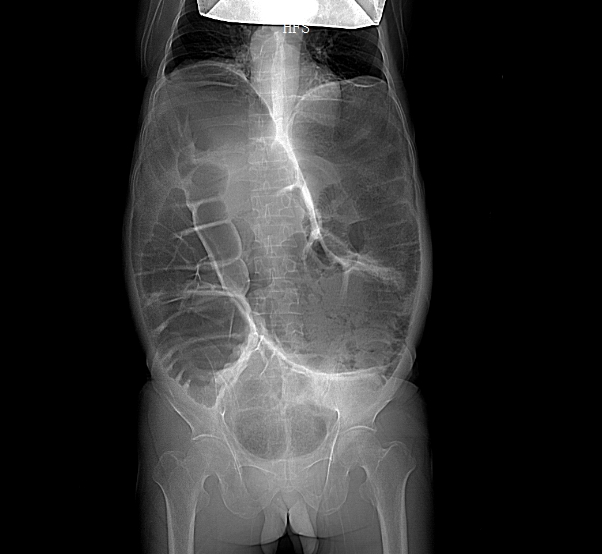

考虑到甘先生身体虚弱,无法配合完成钡灌肠大肠造影,胃肠外科·小儿外科团队给他安排了腹部 CT、DR 和肠镜检查。

结果一出来,答案清晰了:他的升结肠、横结肠显著扩张,像被吹大的气球,胀得异常粗大;可远端的结肠和直肠,却明显狭窄。

结合临床表征,团队初步断定:这不是普通便秘,而是一种罕见病——成人全结肠型巨结肠。